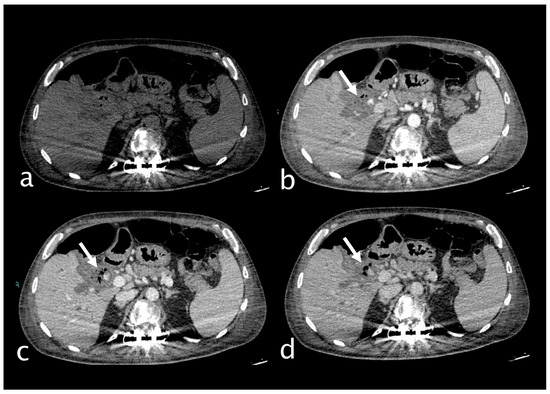

2. Imaging

3.1.3. Imaging and Diagnostic Findings